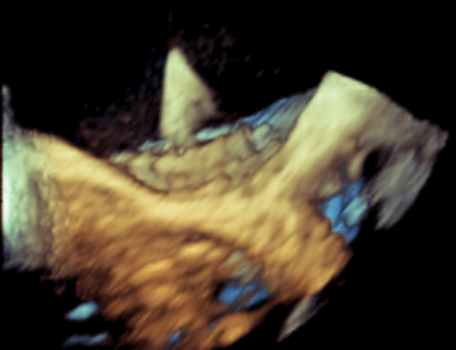

原生物瓣少量反流

过瓣流增快,呈“五彩状”

CDFI提示过瓣血流通畅

CDFI示少量瓣周漏